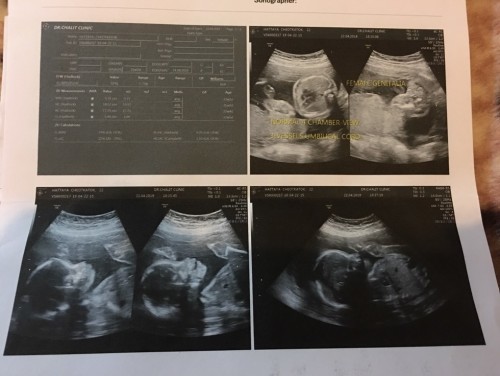

สอบถามแม่ๆหลายท่านค่ะ วันนี้เราไปซาวด์เพศมาคุณหมอบอกได้เพศหญิงค่ะ ไม่ทราบว่าดูเพศตรงไหนหรอค่ะ รบกวนคุณแม่ช่วยดูให้หน่อยค่ะ

ไม่เห็นนะคะ ในผลซาว คุณหมออาจไม่ได้ปริ้นในมุมระหว่างขามาคะ..